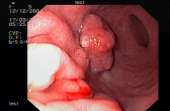

Здоровья анона тредж стартует здесь. Анон, как ты следишь за своим здоровьем? Проходишь ли какие нибудь обследования? Сдаешь ли анализы? Сегодня с утра проходил ЭГДС, последний раз делали эту процедуру лет в 17. Процедура далеко не самая приятная, аноны которые проходили - подтвердят. Зато после неё я спокоен. Нашли поверхностный гастрит и дуоденит, что для моего возраста нормально. Еще до НГ делал МРТ головного мозга, там тоже все в пределах нормы. Разумеется каждый год прохожу флюрографию и набегаю на терапевтов, чтобы те выписали мне анализы. Курил с перерывами лет 5, по 3-5 сигареты в день, бросил, перешел на парение. А что ты, анон, делаешь для своего здоровья?

>>119387366Специально для куребляди. На пике - рак желудка.